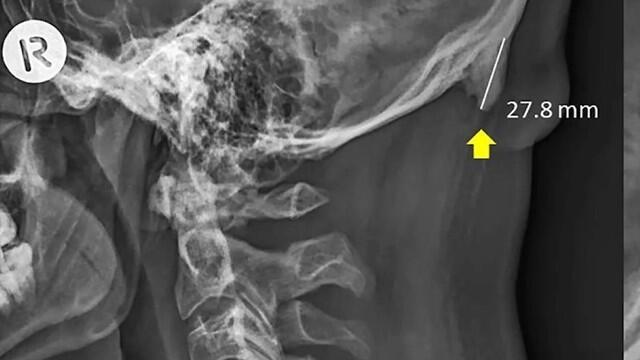

Исследование провели д-р Дэвид Шахар и доцент Марк Сэйерс из австралийского университета Sunshine Coast. Они рассмотрели около 1200 рентгенограмм черепов взрослых людей в возрасте 18-86 лет и обнаружили костные выросты, напоминающие рожки, на задней части черепа.

Их размер составлял 10-31 мм, и чаще всего они наблюдались у молодых мужчин 18-31 года. Некоторые "рожки" были столь большими, что их можно было нащупать.

Ученые предположили, что рожки образовались из-за повышенного давления на шейные мышцы при сгибании головы вниз при использовании сотового телефона. Эта привычка привела к изменениям в скелете, ставшим причиной роста рожек. По похожей причине (механическое воздействие) вырастает пяточная шпора на стопе.